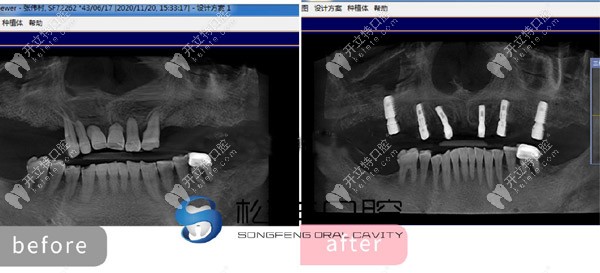

★ 上半口做了6顆即刻負(fù)重種植牙的CT片

上半口做了6顆即刻負(fù)重種植牙的CT片